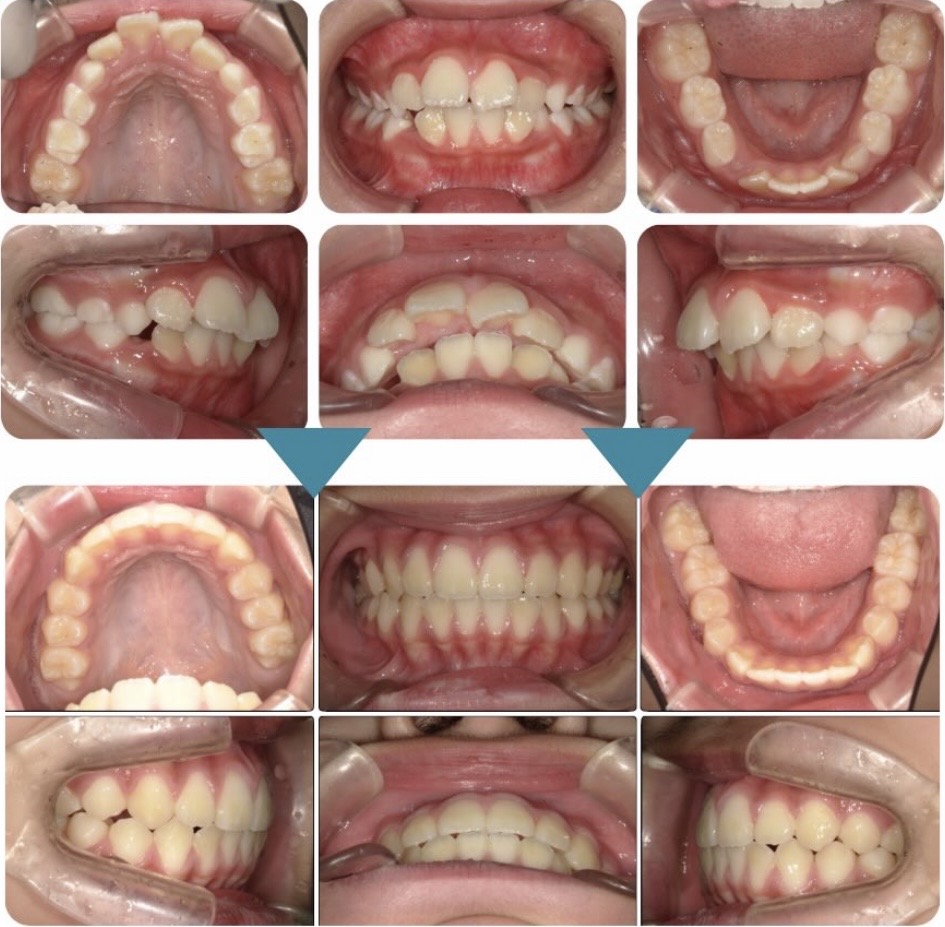

治療前後の比較写真です。

治療前後では下の歯のがたつきはなくなり、上の顎もU字歯列になり綺麗な噛み合わせが保たれています。

大きく見えていた前歯も歯のアーチが綺麗になると気にならなくなりました。

気道写真やレントゲン写真を比較してもしっかりと前方成長できていることがわかります。